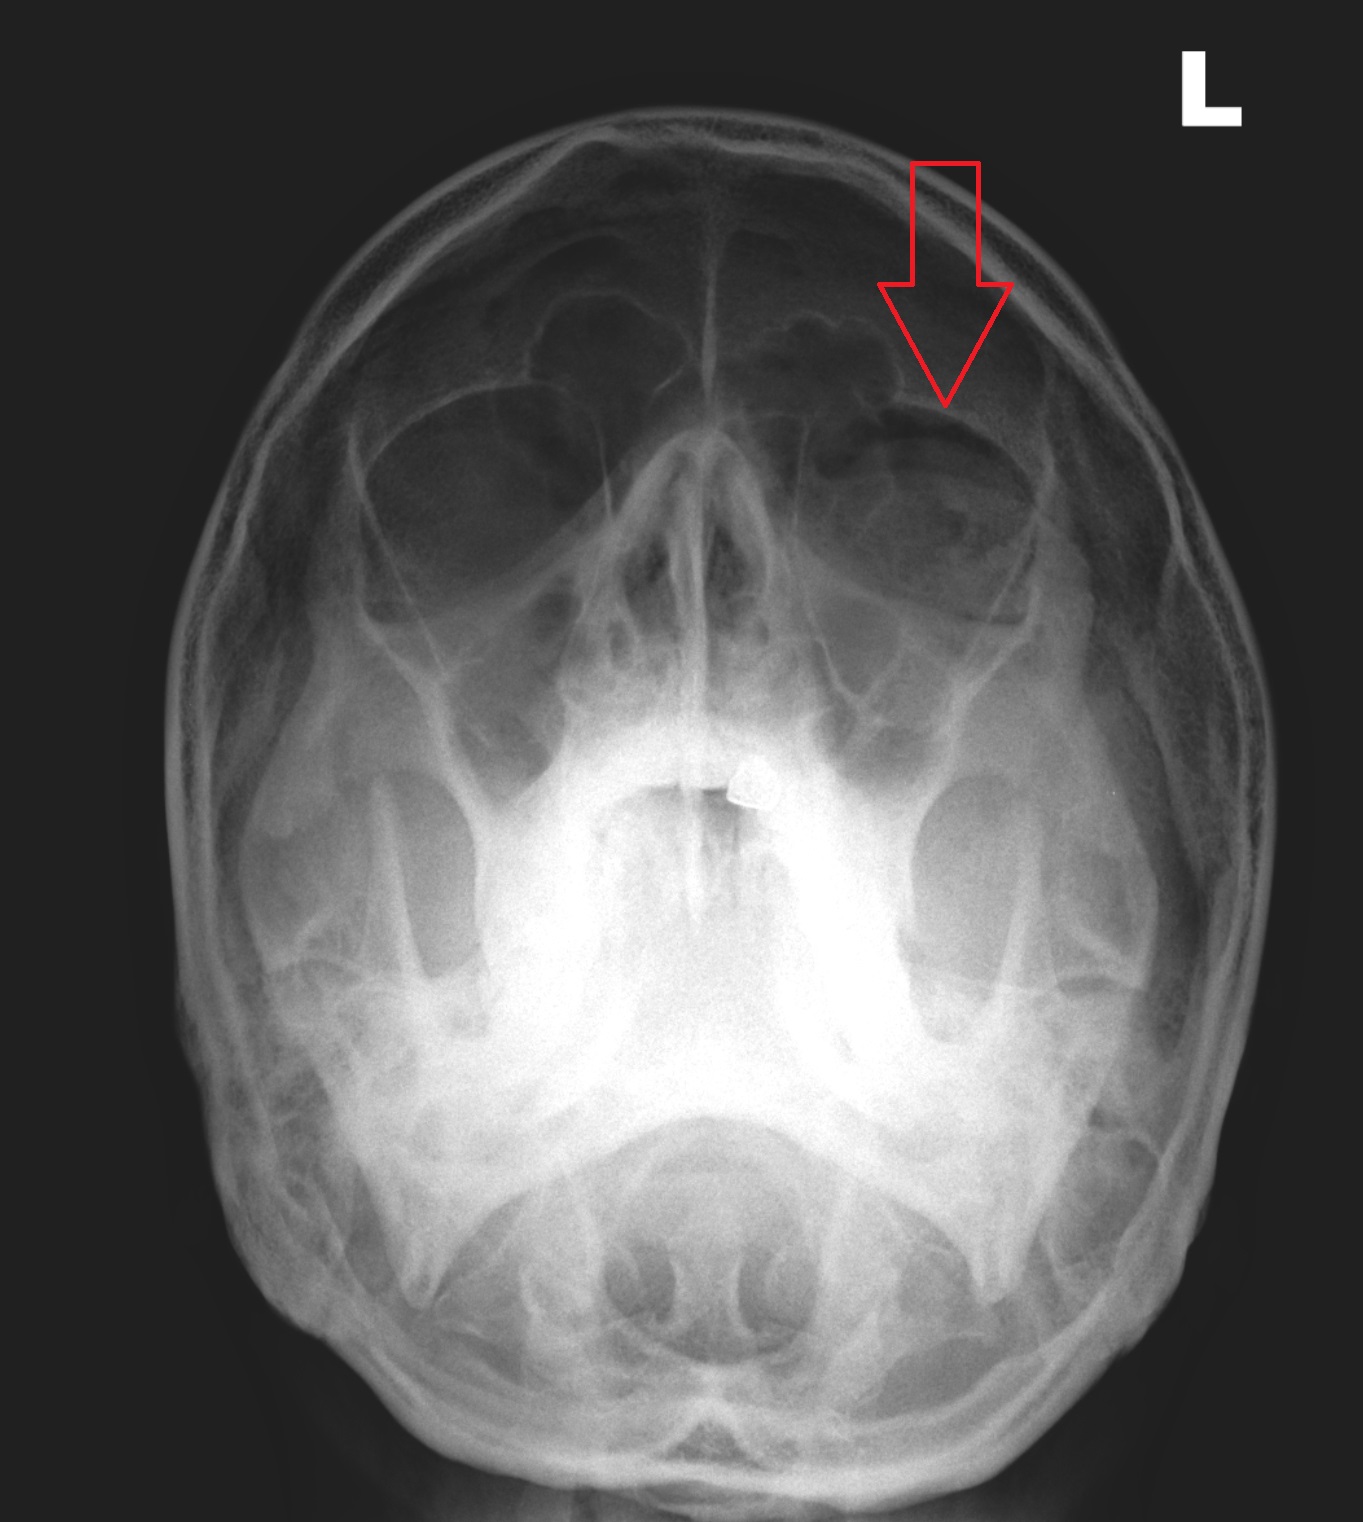

CASE 4

HISTORY

Male aged 23.

Punch injury following a heated argument. Pain in the left side of the face.

QUESTION

Normal or abnormal appearances?

RADIOGRAPHS

ANSWER